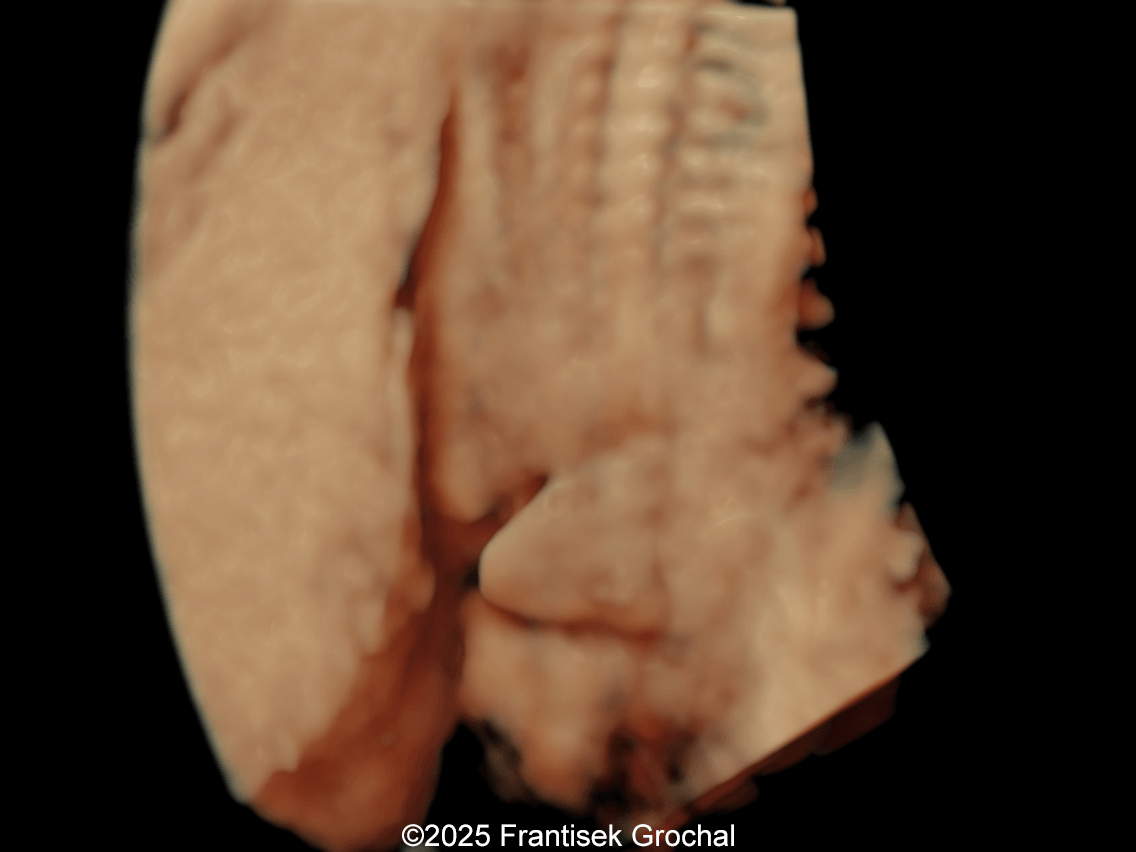

Image 1 Constriction of fetal torso by two stripes of the amniotic bands

Constriction of fetal torso by two stripes of the amniotic bands

Image 3 Constriction of fetal torso by two stripes of the amniotic bands

We present a case of Amniotic Band Sequence seen in 21st week of pregnancy. The fetus showed the following findings:

• Constriction of fetal torso by two strips of amniotic band